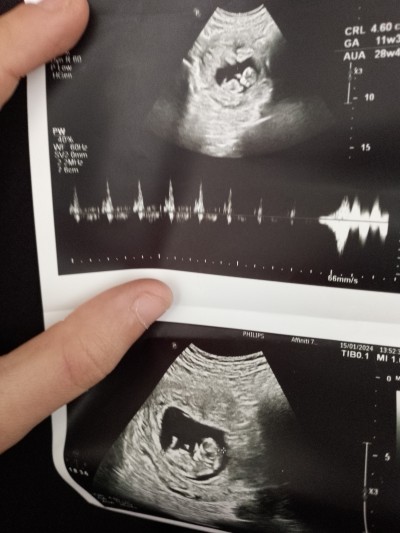

kemik yapısına göre kıza benziyor dedi sizce kız mı erkek mı

İçimden kız geçti

Bence erkek hayırlısı olsun sonucu öğrenince bizimle paylaşmanı bekliyorum